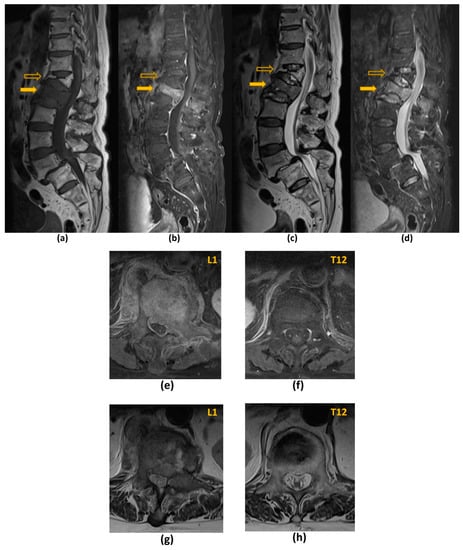

| T2-W | Evaluation of spinal cord and nerve root compression (‘myelogram-like effect’); Detection of cord signal changes (e.g., myelomalacia or oedema) | Suboptimal for evaluation of marrow replacing lesions |

| T1-W | Identification of marrow replacing lesions including metastasis; Useful for comparison with post-contrast sequences to identify true contrast-enhancement | Suboptimal for evaluation of spinal cord and nerve root compression; Peritumoural oedema may also appear hypointense on T1-W sequences, which may limit the accuracy of measurement of the true tumour size |

| T1-W post-contrast FS | Detection of enhancing vertebral metastasis, sites of leptomeningeal and intramedullary disease; Delineation of tumour extent including identification of the epidural component, and presence of foraminal or paraspinal extension; Determination of biopsy site of highest yield (if biopsy required) | Suboptimal for evaluation of spinal cord and nerve root compression |

| STIR | Identification of marrow replacing lesions including metastasis; More accurate measurement of true tumour size from surrounding peritumoural oedema than T1-weighted sequences; Identification of macroscopic fat in lesions | Suboptimal for detection of sclerotic vertebral metastasis without oedema |